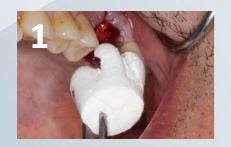

Case courtesy of Tim Kosinski, DDS

• Following extraction, the large size OsteoGen® Plug is contoured to fill the three roots of the socket. Plug is delivered dry into a thoroughly debrided and actively bleeding socket. (Fig. 1)